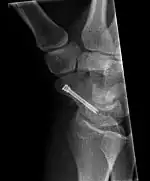

The scaphoid can be slow to heal because of the limited circulation to the bone. Fractures of the scaphoid must be recognized and treated quickly, as prompt treatment by immobilization or surgical fixation increases the likelihood of the bone healing in anatomic alignment, thus avoiding mal-union or non-union.[6] Delays may compromise healing. Failure of the fracture to heal ("non-union") will lead to post-traumatic osteoarthritis of the carpus.[1]: 189 One reason for this is because of the "tenuous" blood supply to the proximal segment.[3] Even rapidly immobilized fractures may require surgical treatment, including use of a headless compression screw such as the Herbert screw to bind the two halves together.